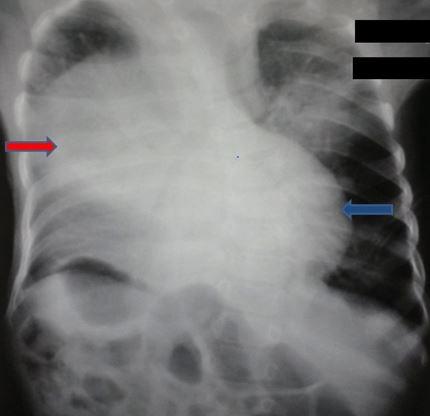

Retro-costo-xyphoidian hernia is a rare congenital malformation. It accounts for 3% of all the diaphragmatic hernias. It can be isolated or associated with other malformations. We here report a very rare case of Morgagni-Larrey hernia and situs inversus totalis detected after neonatal respiratory distress.